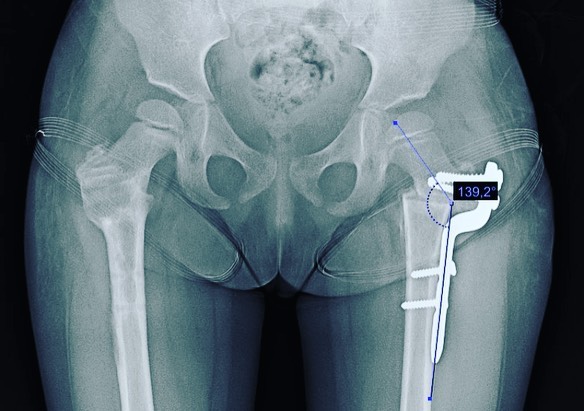

Displasia de cadera

Quiero compartirles que doy de alta a mi pacientita Leilany, de 5 años. La operé por displasia de cadera causada por coxas valgas (región proximal del fémur muy vertical), que alteraba la morfología de su cadera y provocaba disfunción a largo plazo. Le realicé un tratamiento quirúrgico para corregir la deformidad y ahora está al 💯, lista para jugar y hacer travesuras. 🎉